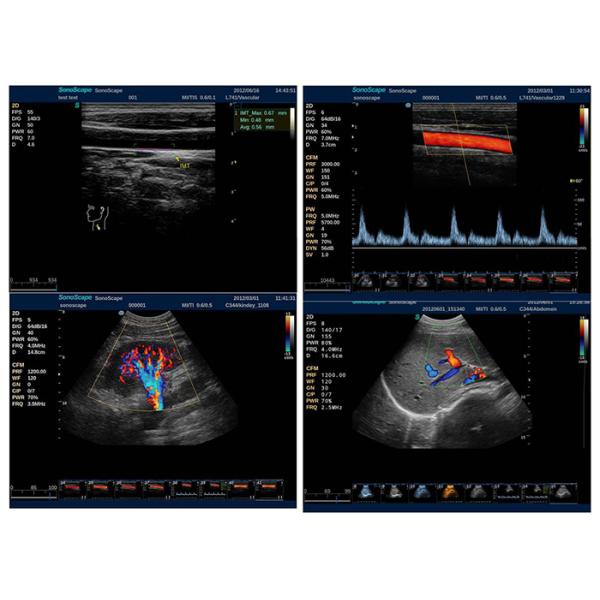

Complete working modes, outstanding 2D performance, sensitive blood flow imaging, 4D image technology, endows S2 with the best package of functions in its class!

4D Ultrasound Equipment With 15 Inch LCD , Color Doppler Ultrasound Machine Images |